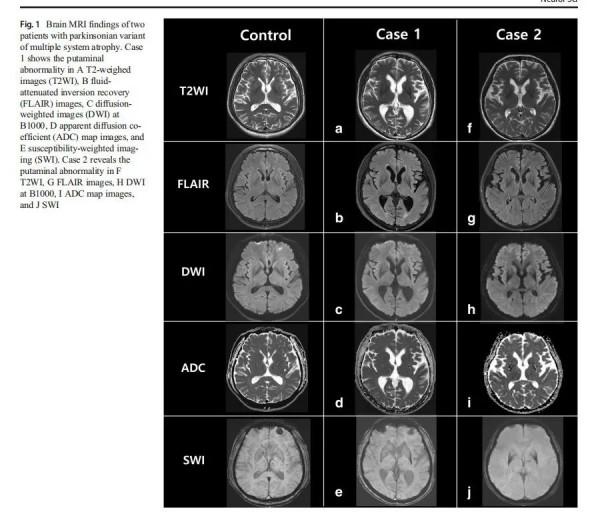

一是影像典型:殼核改變,包括殼核萎縮、殼核背外側低訊號、殼核外緣的裂隙徵都很有特點。不僅傳統的T2相,可以看出SWI、DWI和ADC圖對於殼核異常也很有診斷價值。請看文獻報道的DWI、ADC圖和SWI對MSA的診斷價值。